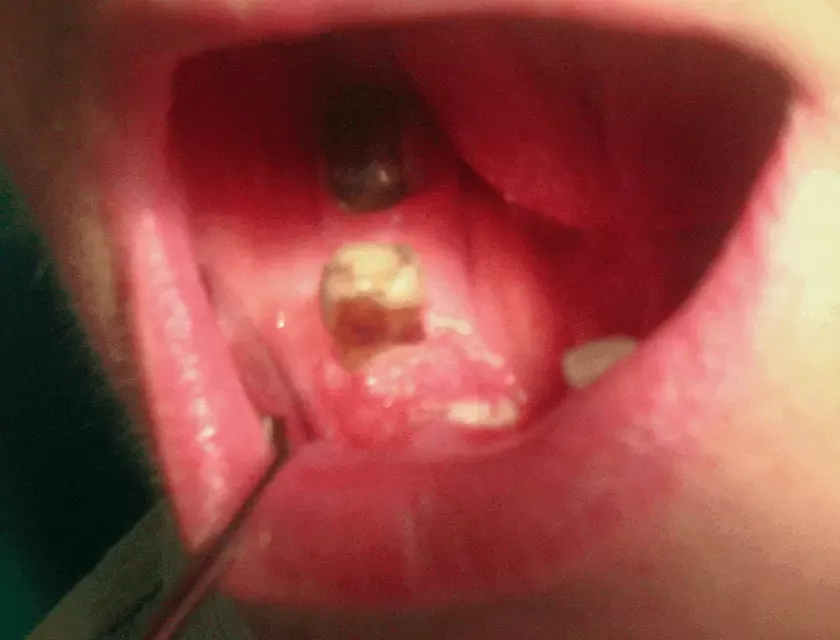

Guzki i owrzodzenia w jamie ustnej: Co powinno niepokoić?

Guzki i owrzodzenia w jamie ustnej to objawy, które mogą wskazywać na nowotwór dziąseł. Guzki mogą mieć różne kształty i rozmiary, a ich obecność często jest pierwszym sygnałem, że coś jest nie tak. Owrzodzenia, które nie ustępują, również powinny budzić niepokój. Warto zwracać uwagę na wszelkie zmiany w tkankach dziąseł oraz błonie śluzowej jamy ustnej.

Rozpoznanie guzków i owrzodzeń można przeprowadzić samodzielnie, ale najlepiej skonsultować się z lekarzem. Niekiedy mogą one być bolesne lub powodować dyskomfort, co dodatkowo powinno skłonić do wizyty u specjalisty. Niezależnie od tego, czy zmiany są bolesne, czy nie, ich obecność zawsze powinna być zgłoszona lekarzowi.

- Guzki w jamie ustnej: Niekiedy mogą być twarde lub miękkie, a ich obecność powinna budzić niepokój.

- Owrzodzenia: Rany, które nie goją się przez dłuższy czas, mogą być oznaką nowotworu.

- Krwawienie dziąseł: Szczególnie, gdy występuje bez wyraźnej przyczyny, może wskazywać na poważny problem zdrowotny.